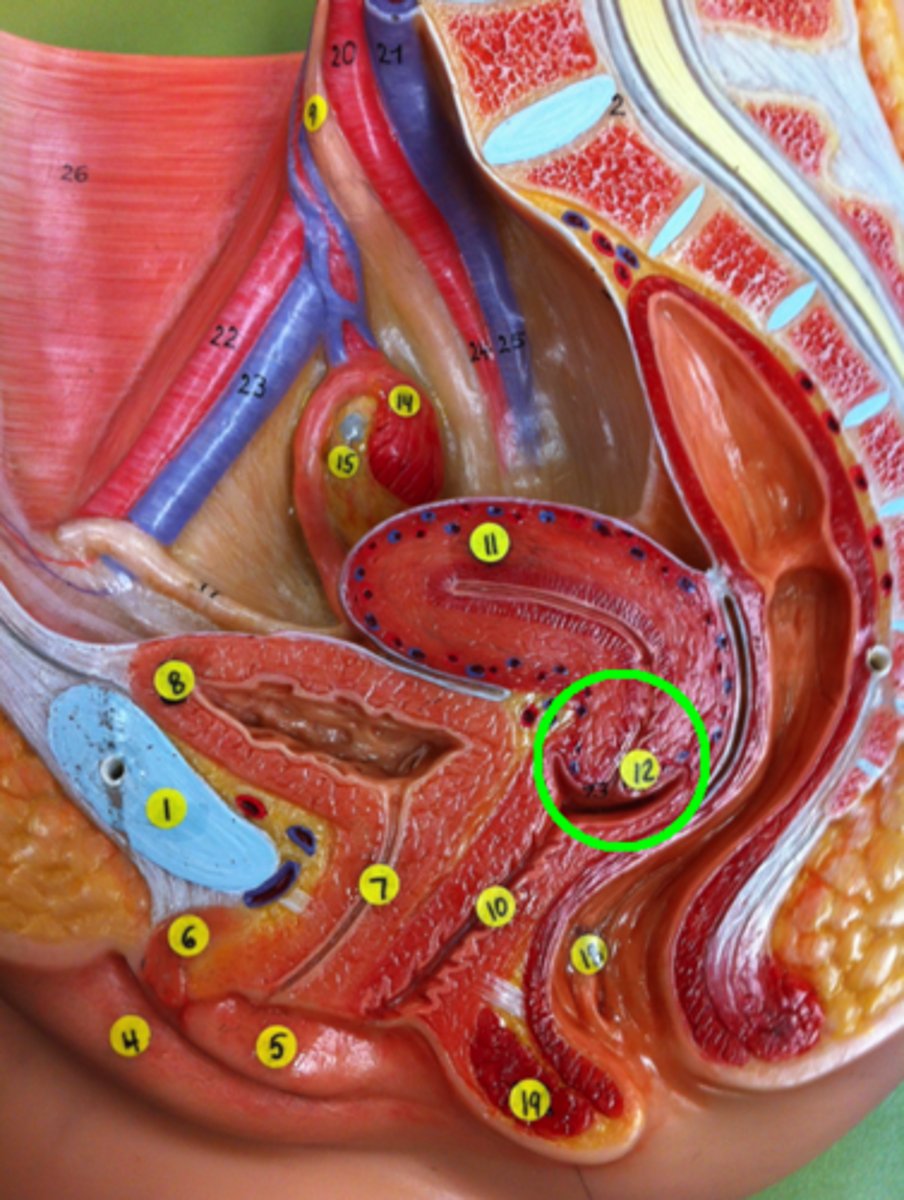

Cervix of Uterus